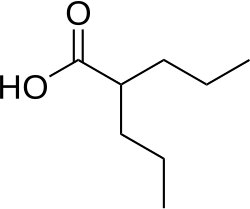

Additionally, experiments using mouse embryonic stem cell-derived neural progenitors showed that increased histone deacetylase, induced by the HDAC inhibitor valproic acid, not only promoted neuronal differentiation but also selectively enriched the upper-layer neuronal population. This has led to the proposal that HDAC inhibition may drive a fate-switch from progenitors that produce deep-layer neurons to those that generate upper-layer neurons. However, the mechanisms behind this selective differentiation and the timing control associated with HDAC inhibition remain not fully understood.[2]

Histone deacetylase inhibitors (HDACi)—such as valproic acid (VPA) and trichostatin A—can enhance adult neurogenesis by blocking HDAC activity, which promotes the differentiation of adult neural progenitor cells.[19] In neural stem cells, HDAC1 and HDAC2 work with the transcription factor TLX to suppress genes that limit cell proliferation, including the cell cycle inhibitor P21 and the tumor suppressor Pten.[20] This repression supports the self-renewal and proliferation of neural stem cells. However, when HDACs are inhibited—such as by VPA, an antiepileptic drug—it can shift neural stem cells toward neuronal differentiation. Similar to processes seen in embryonic neurogenesis, VPA can also suppresses glial cell differentiation in adult neural stem cells. This effect is likely driven by the upregulation of neuron-specific genes, including neurogenic basic helix-loop-helix (bHLH) transcription factors like NEUROD, NEUROGENIN1, and MATH1. While HDAC inhibition can promote neurogenesis, complete loss of HDAC1 and HDAC2 in neural progenitor cells has the opposite effect, potentially preventing proper neuronal differentiation. Similarly, their loss in oligodendrocyte progenitor cells disrupts oligodendrocyte formation, highlighting that histone deacetylation plays distinct and essential roles at various stages of neural development.

It has been thought that HDAC inhibitors (HDACi's) could partially reverse the low acetylation levels seen in patients with HD. Preclinical studies have been performed using various HDACi's [such as suberoxylanilide hydroxamic acid (SAHA), Trichostatin A (TSA), phenylbutyrate, and sodium butyrate (NaB)] that target HDACI and HDACII. Although these inhibitors improve some phenotypes of HD in mice, such as neuropathology and motor function, these beneficial effects do not lead towards a conclusion for the definitive need for increasing acetylation levels in HD patients. Recent findings suggest that HDAC inhibition may not only affect histone proteins but also modulate non-histone targets involved in neuronal survival, axonal transport, and protein aggregation.[34]

As of 2014, HDACi treatment has not been shown to restore normal expression of neuronal-identity genes.[47] However clinical studies using HDACi are currently ongoing and the results are pending, with the Phase II studies showing promise for safe and tolerable use of several compounds such as phenylbutyrate. Newer approaches are investigating more selective HDAC inhibitors that target specific isoforms, aiming to minimize off-target effects while maximizing therapeutic benefits.[34]

Given the growing evidence of epigenetic involvement in neurological and psychiatric disorders, researchers are investigating epigenetic-based therapies. HDAC inhibitors, such as valproic acid and vorinostat, have been explored as potential treatments for Alzheimer's, Parkinson's, and Huntington's diseases due to their ability to enhance gene expression related to neuronal survival and synaptic plasticity.[34]